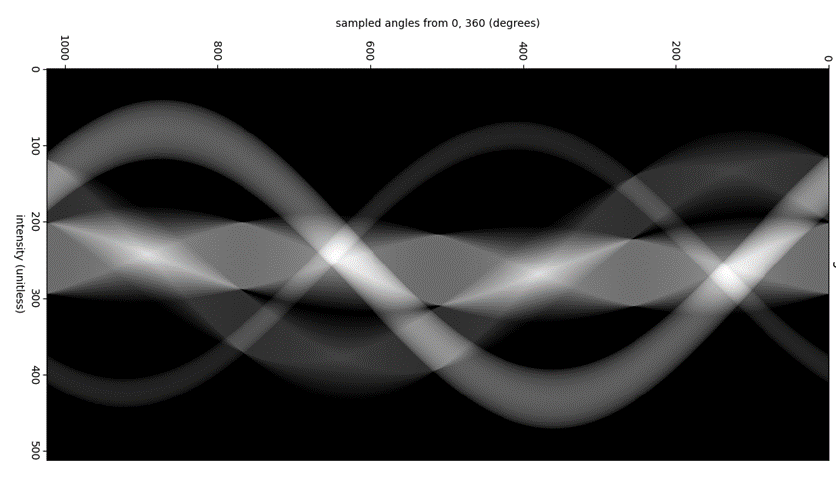

Image reconstruct works because of the “Fourier projection theorem” or Projection-slice theorem” [13]. This theorem states that the integral of a shape projection along some axis is a slice of the 2d Fourier transform of that shape projected along the same axis. A graphical view of this theorem can be seen in Figure 1. This method is called back projection. Plotting all these back projected angles creates a sinogram and example of which can be seen in Figure 2. This figure shows sinogram of a basic test image that can be found in Appendix B: basic image This theorem also states that an infinite number of projects are taken at different angles and the image can be perfectly reconstructed.

Figure 2: sinogram of basic image

Figure 2: sinogram of basic image

As can be seen in this Figure 2: sinogram of basic image the sinogram is mirror at the 180° mark, however it is mirrored both horizontally and vertically. using this knowledge this means that when taking the back projections of an object, only must take the back projections of the object from 0 to 180 degrees to have enough data to reconstruct the object. To take these back projected and reconstructed the image from them a method must be used called forward projection. This technique takes the slice and angle and project the values at that angle across the image plane, as can be seen in Figure 3.